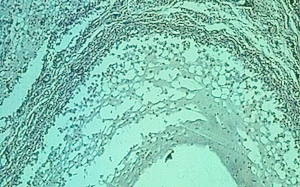

Atlas of skin histopathology

Mucus Retention =الأحتباس المخاطي